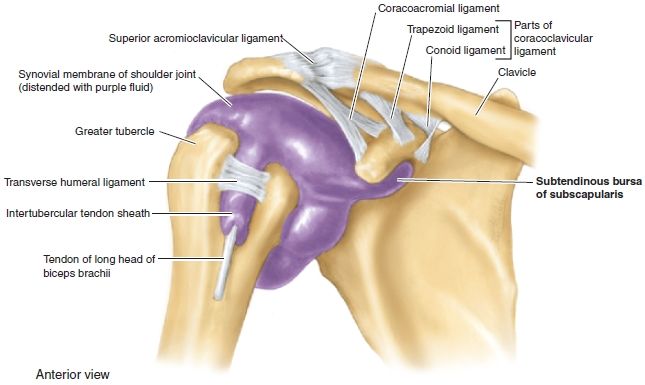

Glenohumeral ligament: анатомия и функции плечевого сустава